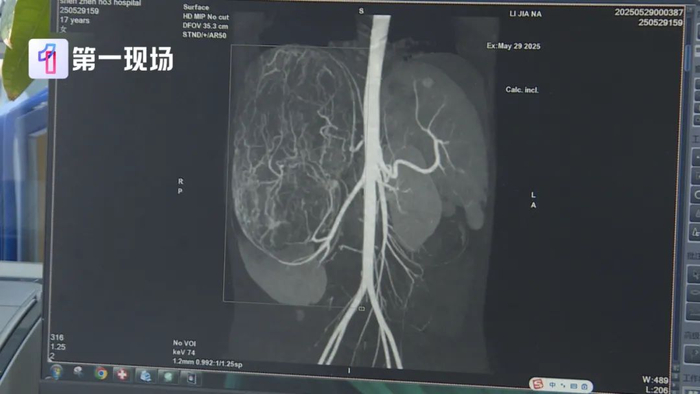

一查吓一跳,婷婷的肚子里,竟然长了一个巨大的肿瘤,肿瘤直径长达27厘米。

等到了当地医院一检查,CT结果显示,她的右肾有恶性肿瘤伴肝转移可能,家长就立即带着孩子来到深圳求医。

但肿瘤体积过大,几乎占据了整个腹腔,周边器官也被严重挤压,留给医生的手术空间实在有限。经过多轮讨论,最终,医生决定创新尝试国外的“反L型”切口开腹策略。